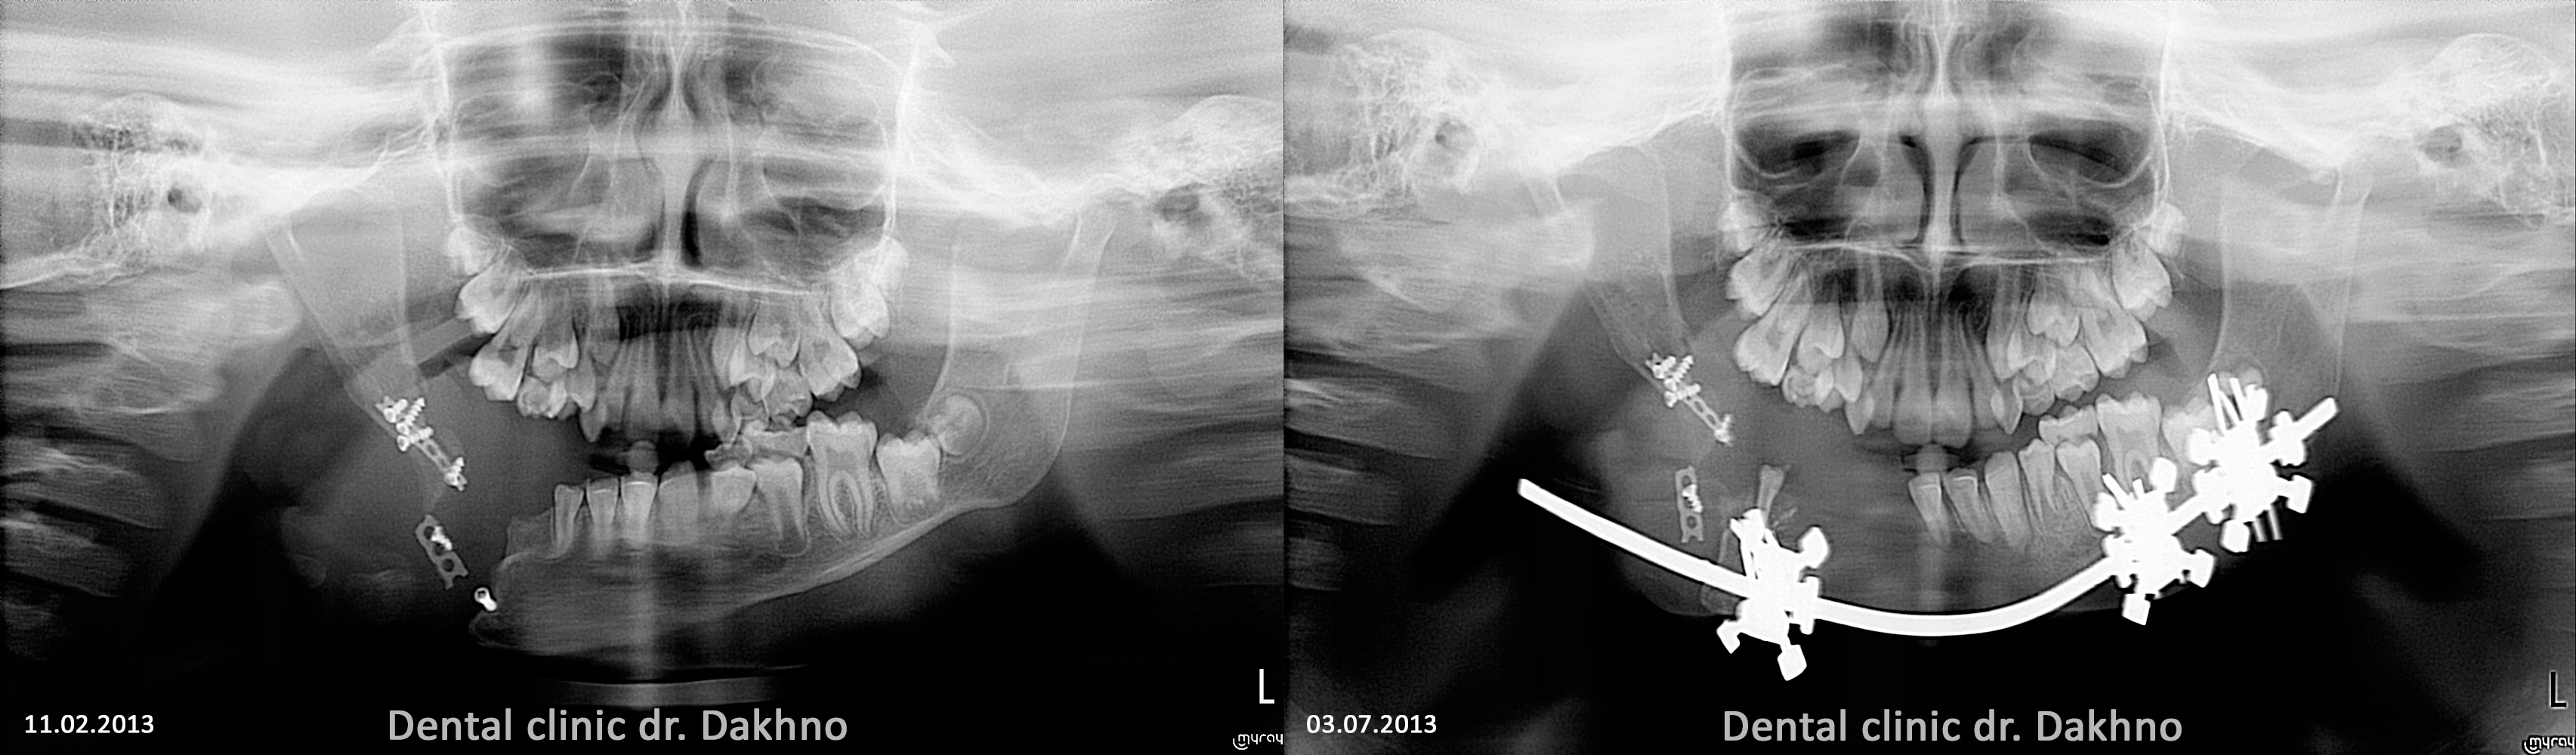

Клінічний діагноз: післяопераційна деформація нижньої щелепи. Сформований постдістракційний псевдосуглоб в області кута нижньої щелепи справа. Вторинна зубо-альвеолярна і скелетна деформація. Обмеження відкривання рота.

2013 рік – дистракційний остегенез, поставлена фіксуюча пластина. Пластина була встановлена двічі, так як м’язова сила приводила до перелому пластин на рівні кута щелепи.

На даний момент Дарині встановлена брекет-система, за допомогою якої проводиться підготовче лікування для щелепно-лицевої хірургії.

У ортодонтичне лікування підключені всі наявні в зубних рядах зуби. Для апрайтінга групи зубів нижньої щелепи впроваджений мікроімплант (як скелетна опора (TAD)